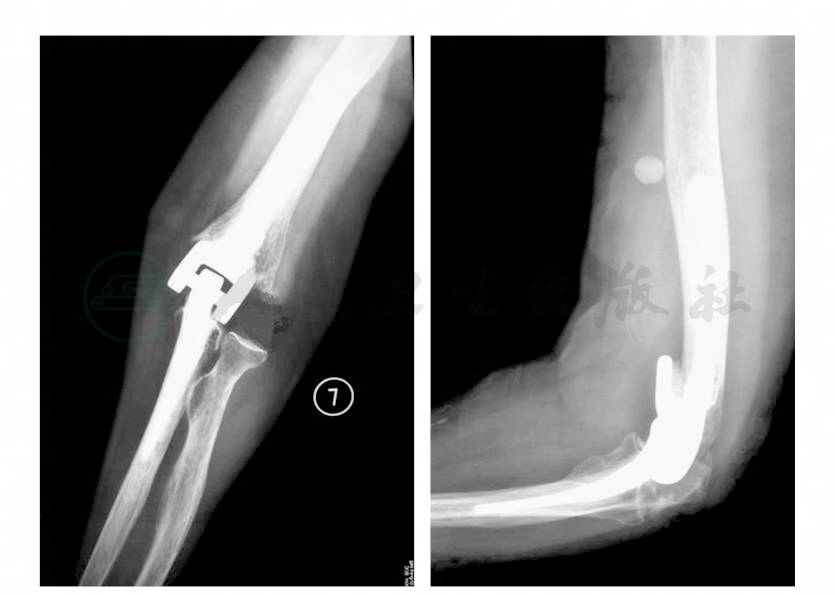

患者术后第2日移除伤口引流管,行X线检查示假体位置良好(图3)。在术后第2天开始不提重的主动活动,并使用颈腕吊带保护3周,不做任何活动度的强力训练,最初3个月内所提物体重量不得超过0.5kg,以后患肢所提重量也不得超过2.5kg。

图3 术后肘关节X线片